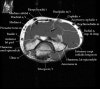

팔꿈치 관절의 MRI 단면 영상

2. Axial section

1) The tendons of the Biceps Brachii and Brachiallis muscles transversely as they insert onto the Radius and Ulna respectively. 2) The distal Triceps tendon is also well evlauated in this plane.